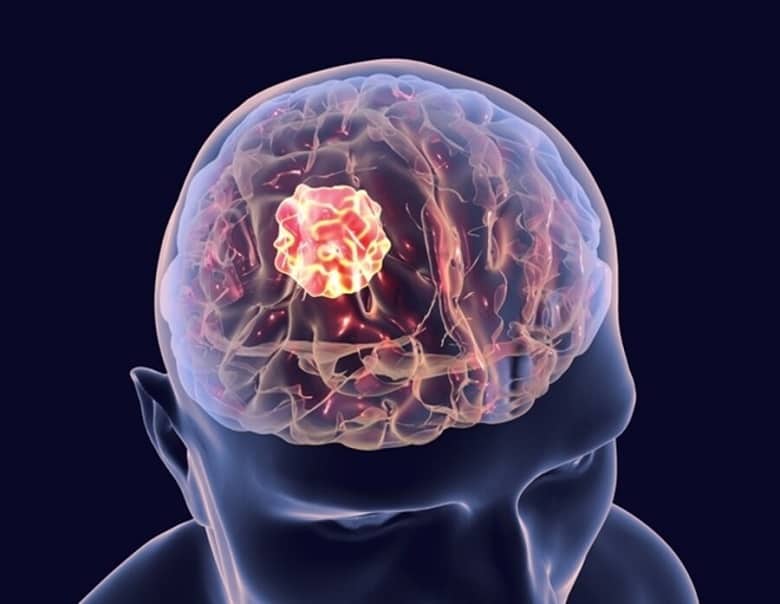

به گزارش وقت صبح به نقل از خبرآنلاین، علائم بالقوه زیادی برای تومورهای مغزی وجود دارد، اما فردی که تومور مغزی دارد بعید است که همه این علائم را داشته باشد. همچنین، بسته به محل رشد تومور در مغز و بزرگی آن، علائم متفاوت است.

علائم تومورهای مغزی بسته به نوع، اندازه و محل دقیق مغز متفاوت است. برخی از علائم هشدار دهنده تومور مغزی شامل موارد زیر است:

تومورهای مغزی میتوانند بر ساختارهای مغز فشار وارد کنند. این اتفاق میتواند با سیگنالهای الکتریکی بین سلولهای عصبی تداخل کند و منجر به تشنج شود.

تشنج گاهی اوقات اولین علامت تومور مغزی است، اما ممکن است در هر مرحلهای رخ دهد. حدود ۵۰ درصد از افراد مبتلا به تومور مغزی حداقل یک تشنج را تجربه میکنند.